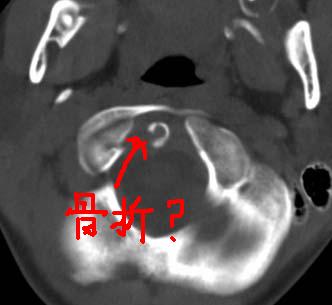

患者在校与同龄孩子打闹后(据家长说被拳击中颈部)出现颈部不适30分钟后入院检查,来时脖子歪斜。请大家看看枢椎齿状突及寰枢关节有问题吗?(3mm层厚断层扫描)。

未见异常

未见明显异常

未见明显异常.再查mri看看。